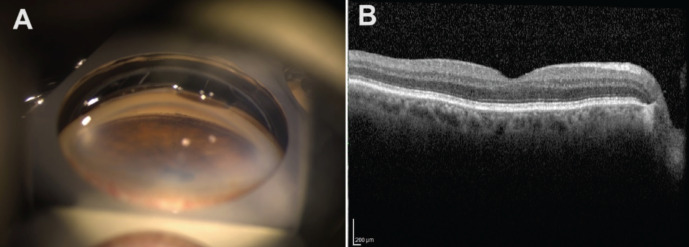

Cataract surgery is the most frequently performed surgery worldwide. Although it is an effective surgical treatment option for improving patients' visual acuity, various complications can occur postoperatively. One such complication is the presence of retained lens material in the anterior chamber, which can lead to intraocular inflammation, increased intraocular pressure, corneal edema, and endothelial cell loss. Treatment options include observation and surgical removal of the retained lens material. Another notable treatment option is the use of neodymium-doped yttrium aluminum garnet (Nd:YAG) laser to fragment the retained lens material. In this paper, we aim to present two cases from our clinic where Nd:YAG laser treatment was applied to patients with retained small lens fragments in the anterior chamber following cataract surgery. It was observed that in both patients, the retained lens fragments were resorbed by the first day after Nd:YAG laser treatment, and no complications developed.